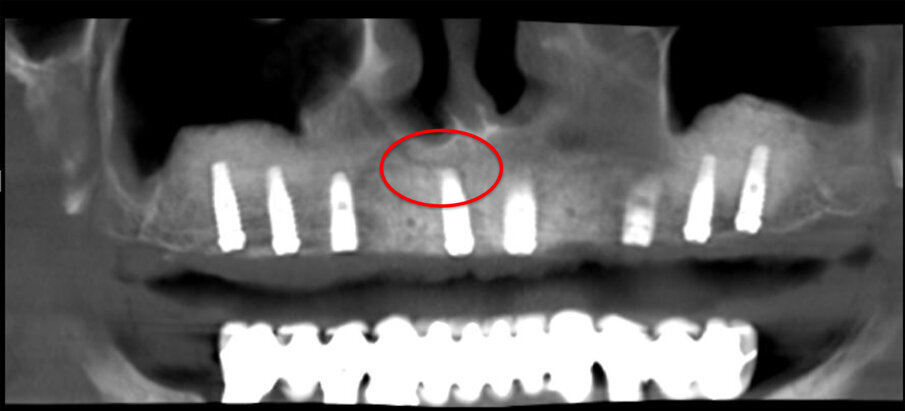

Una paziente di 62 anni, ASA 1 si rivolge alla nostra attenzione per richiedere una riabilitazione dell’arcata mascellare superiore essendo portatrice di protesi mobile totale. L’esame radiologico iniziale evidenzia una marcata atrofia ossea quindi viene progettato l’inserimento di 8 impianti dopo elevazione bilaterale dei seni mascellari al fine di realizzare un a protesi tipo Toronto-Bridge. Trascorsi 8 mesi dai sinus lift e dopo aver accertato la totale guarigione dei siti innestati con una CBCT viene eseguito l’intervento implantare in anestesia locale, sotto profilassi antibiotica, con chiusura dei lembi per prima intenzione e senza eseguire procedure di carico immediato. La paziente viene quindi controllata regolarmente ed a distanza di 7 giorni manifesta una sintomatologia algica localizzata alla zona 1.1 che inizialmente appariva compatibile con il normale decorso post-operatorio. Successivamente a 15 giorni la situazione era nettamente peggiorata trasformandosi in dolore localizzato e persistente con acutizzazioni che la paziente descriveva come “scosse elettriche” o “stilettate”. A questo punto è stata eseguita una nuova analisi della CBCT postoperatoria (Fig. 5) al fine di indagare in maniera più approfondita tale zona, l’analisi delle immagini ha evidenziato la presenza di un CS destro compresso dall’apice dell’impianto in posizione 1.1 (Figg. 6, 7). Tale condizione veniva subito riconosciuta compatibile con la sintomatologia della paziente e si procedeva a rimuovere e sostituire la fixture con una di lunghezza inferiore che non interessasse il decorso del CS (Fig. 8). Veniva quindi prescritta una terapia farmacologica post-operatoria comprensiva di antibiotici, antinfiammatori ed integratori di complessi vitaminici B. La paziente è stata controllata giornalmente manifestando un graduale miglioramento fino a scomparsa della sintomatologia algica a 15 giorni.

Fig. 5 - Panorex Postoperatoria con CS in evidenza.